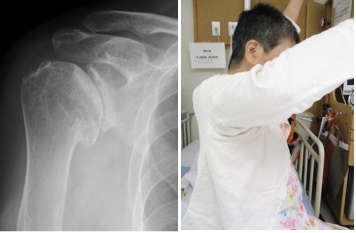

術前

右肩の変形と挙上制限を認めます

術後

人工関節で痛みや可動域が改善しました